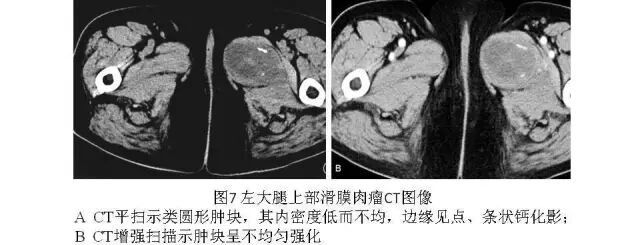

2.CT

可较清楚显示肿块的大小、范围与周围组织的关系以及X线片难以显示的钙化。CT平扫呈圆形或分叶状肿块,边界清楚,密度多低于肌肉且多不均匀,内见更低密度的液化、坏死及高密度出血区;约20%~40%的滑膜肉瘤可见钙化,钙化常位于病灶的周边,称为边缘性钙化(图7、图8),是滑膜肉瘤CT特征性表现。CT增强扫描肿瘤多呈不均匀强化(图7)或呈渐进性强化,少数肿瘤周围可见异常增粗的血管。